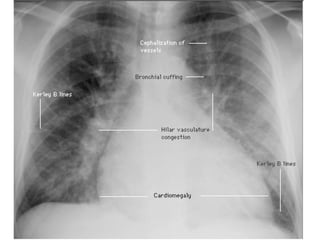

CXR- pulmonary edema Describe?  Perihilar shadowing (bat’s wings)= alveolar edema Upper lobe diversion Kerley B lines= interstitial edema Cardiomegaly (LVF) Pleural effusion? Dx? Pulmonary edema Causes? Cardiogenic: LVF, mitral stenosis, arrhythmias Non-cardiogenic: acute lung injury/ARDS, sepsis, nephrotic/RF/LF

CXR- pulmonary edemaDescribe? Perihilar shadowing (bat’s wings)= alveolar edema Upper lobe diversion Kerley B lines= interstitial edema Cardiomegaly (LVF) Pleural effusion? Dx? Pulmonary edema Causes? Cardiogenic: LVF, mitral stenosis, arrhythmias Non-cardiogenic: acute lung injury/ARDS, sepsis, nephrotic/RF/LF